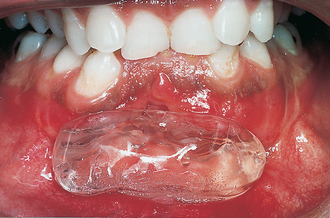

Swelling is a common presenting complaint and if extensive can cause both intraoral and extraoral asymmetry. Importantly the swelling is normally clinically discrete and well demarcated. Where there has been extensive expansion of the cyst the overlying bone will be thin or absent. In the former, the surface will feel firm but flexible, but if the overlying bone has been completely eroded it will appear as a tense bluish swelling that feels ‘fluctuant’ (Fig. 9.4) (see Ch. 7 for a description of fluctuance).

image

Fig. 9.4 Bluish swelling associated with an eruption cyst on a lower first molar.